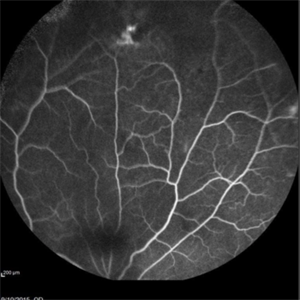

Angiography showed normal vessels posteriorly but severe capillary drop out throughout the periphery OU with scattered severe neovascularization at the edge of the capillary drop out peripherally.

Sickle Cell Retinopathy Sickle Cell RetinopathySep 13 2015 by Thomas A. Ciulla, MD, MBA, FASRS Angiography showed normal vessels posteriorly but severe capillary drop out throughout the periphery OU with scattered severe neovascularization at the edge of the capillary drop out peripherally. Photographer: Thomas Steele Condition/keywords: peripheral retinal neovascularization, sea fan, sickle cell retinopathy